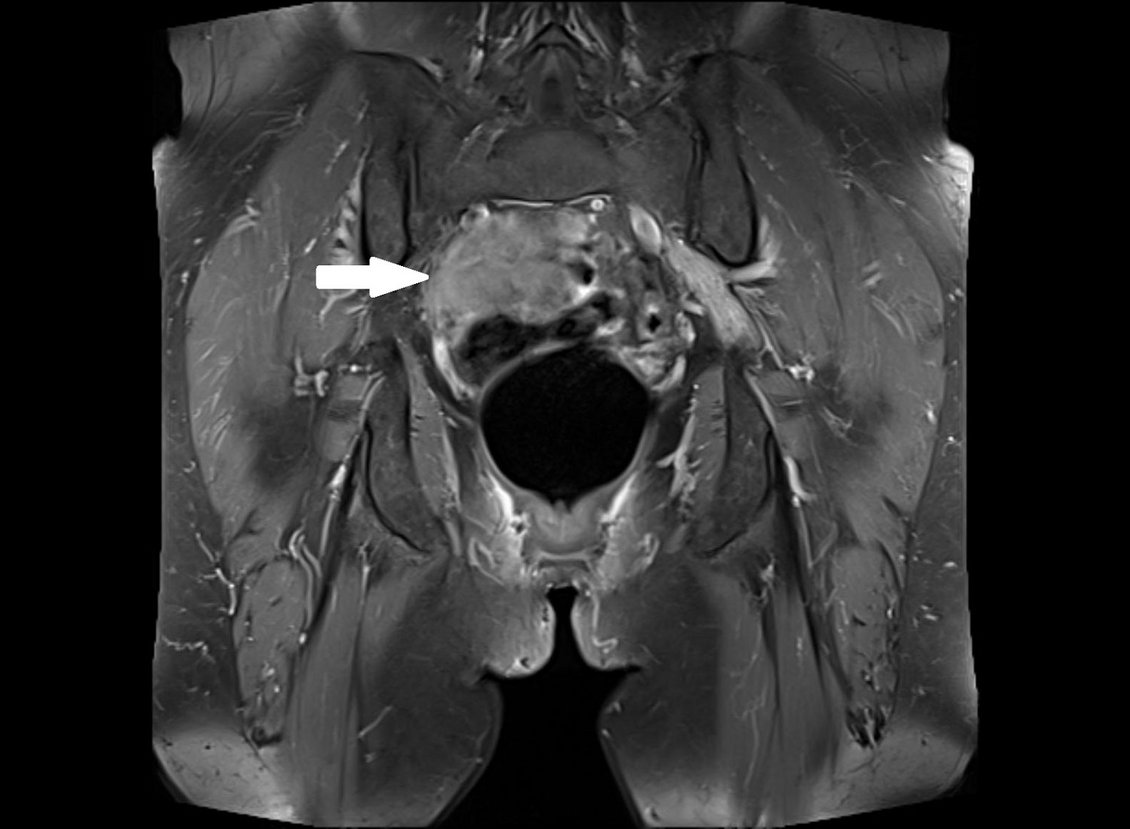

Tumore peripherer Nerven gehen von der Nervenscheidewand aus und sind meist gutartig. Hierzu zählen Neurinome/Schwannome und Neurofibrome, seltener treten bösartige(maligne) periphere Nervenscheidentumore auf. Verlaufen periphere Nerven durch einen von ihnen unabhängigen Tumor bzw. werden sie von diesem verdrängt, entsteht dadurch Druck auf den Nerven. Die Symptomatik ist abhängig von der Tumorlokalisation, typisch sind elektrisierende Missempfindungen, Schmerzen, Taubheitsgefühle und Lähmungserscheinungen.